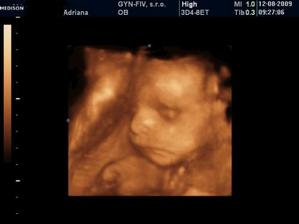

3.6. Uzasny 3D ultrazvuk...Videli sme nasho mimiska... Meriame bez noziciek 10 cm a s nozickami skoro 15 cm... 🙂 A doktor nas prekvapill, ze vraj to bude chlapcek... 🙂 14.7. morfologicky ultrazvuk, vsetko zatial vyzera v poriadku - tesime sa na Andrejka 🙂 12.8. 3D ultrazvuk - ma to 35 cm a 900 gramov, kto je to? No predsa ja Andrejko... 🙂